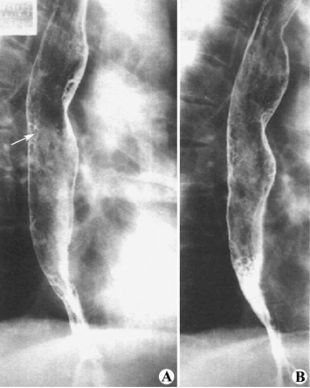

食管静脉曲张:蚯蚓样、串珠状。

食管重度静脉曲张

食管静脉曲张:食管黏膜呈现蚯蚓状

这是食管静脉曲张伴胃底静脉曲张的图像